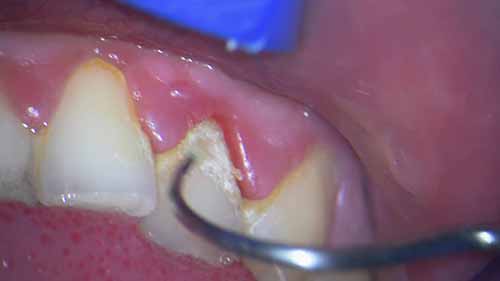

简介:正畸头帽是矫正错牙合畸形常用的一种口外矫正装置。医生们根据患者的年龄和畸形程度来预备头帽。

牙龈出血的原因

仔细观看视频,了解牙龈出血的原因,以及去除牙斑菌和牙结石的重要性和方法。